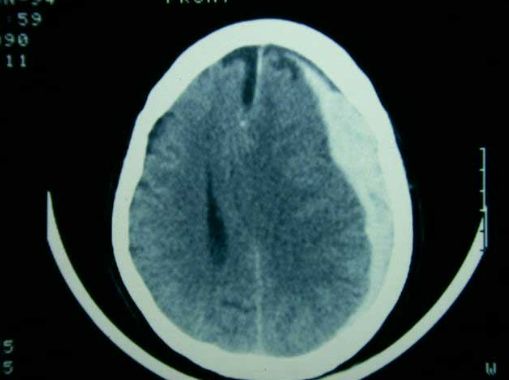

Cómo se diagnostica un hematoma subdural

Ante la sospecha de esta afección, los médicos recurren a estudios por imágenes como la tomografía computarizada o la resonancia magnética, que permiten confirmar el diagnóstico y evaluar la extensión del sangrado.